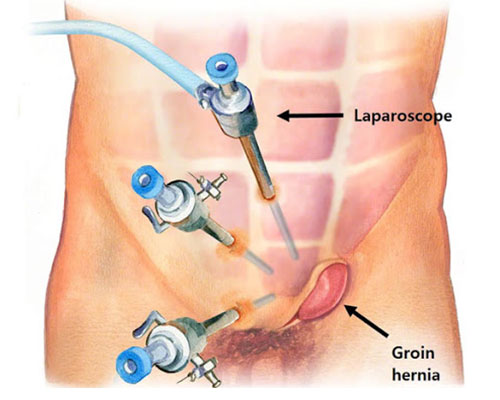

Overview

Package includes:

Days in hospital : 3 to 4 Days (For patient and one attendant)

Days in hotel : 15 Days (For patient and one attendant)

Room type in hospital : Shared

Room type in hotel : Private

Hotel category: Standard

Value added benefits of the Herniorrhaphy - Inguinal - Unilateral:

Ø Doctor consultation charges

Ø Lab tests and diagnostic charges

Ø Room charges inside hospital during the procedure

Ø Surgeon Fee

Ø Nursing charges

Ø Hospital surgery suite charges

Ø Anesthesia charges

Ø Routine medicines and routine consumables (bandages, dressings etc.)

Ø Food and Beverages inside hospital stay for patient and one attendant.

Overview

Package includes:

Days in hospital : 3 to 4 Days (For patient and one attendant)

Days in hotel : 15 Days (For patient and one attendant)

Room type in hospital : Shared

Room type in hotel : Private

Hotel category: Standard

Value added benefits of the Hernioplasty Inguinal with Mesh:

Ø Doctor consultation charges

Ø Lab tests and diagnostic charges

Ø Room charges inside hospital during the procedure

Ø Surgeon Fee

Ø Nursing charges

Ø Hospital surgery suite charges

Ø Anesthesia charges

Ø Routine medicines and routine consumables (bandages, dressings etc.)

Ø Food and Beverages inside hospital stay for patient and one attendant.

Overview

Package includes:

Days in hospital : 2 to 3 Days (For patient and one attendant)

Days in hotel : 15 Days (For patient and one attendant)

Room type in hospital : Shared

Room type in hotel : Private

Hotel category: Standard

Value added benefits of the Hernioplasty Inguinal Bilateral with mesh:

Ø Doctor consultation charges

Ø Lab tests and diagnostic charges

Ø Room charges inside hospital during the procedure

Ø Surgeon Fee

Ø Nursing charges

Ø Hospital surgery suite charges

Ø Anesthesia charges

Ø Routine medicines and routine consumables (bandages, dressings etc.)

Ø Food and Beverages inside hospital stay for patient and one attendant.